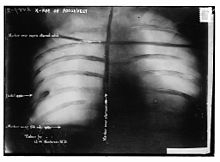

Assassination attempt

While Roosevelt was campaigning in Milwaukee, Wisconsin, on October 14, 1912, a saloonkeeper named John Schrank shot him, but the bullet lodged in his chest only after penetrating his steel eyeglass case and passing through a thick (50 pages) single-folded copy of the speech he was carrying in his jacket. Roosevelt, as an experienced hunter and anatomist, correctly concluded that since he was not coughing blood, the bullet had not completely penetrated the chest wall to his lung, and so declined suggestions he go to the hospital immediately. Instead, he delivered his scheduled speech with blood seeping into his shirt. He spoke for 90 minutes. His opening comments to the gathered crowd were, "Ladies and gentlemen, I don't know whether you fully understand that I have just been shot; but it takes more than that to kill a Bull Moose." Afterwards, probes and x-ray showed that the bullet had traversed three inches (76 mm) of tissue and lodged in Roosevelt's chest muscle but did not penetrate the pleura, and it would be more dangerous to attempt to remove the bullet than to leave it in place. Roosevelt carried it with him for the rest of his life.